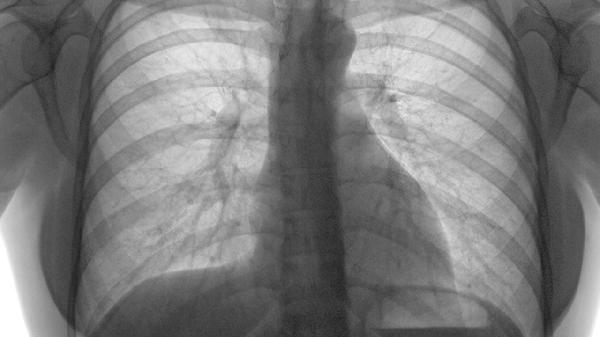

该功效针对肺部良性结节或炎症性肿块,通过软坚散结作用促进病灶吸收。需配合影像学检查定期评估疗效,不可自行用于恶性肿瘤。出现结节增大或性质不明时须立即停药就医。